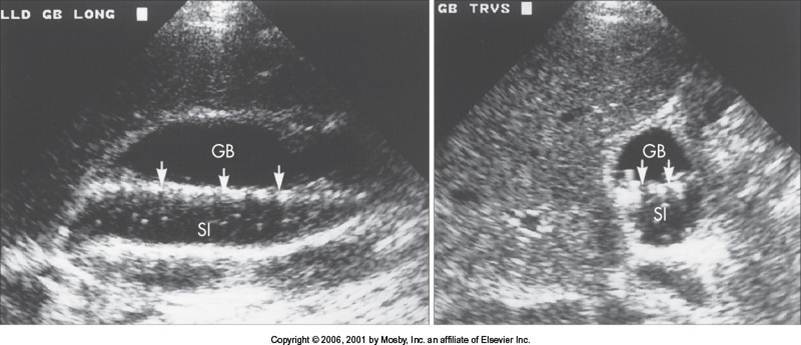

Cholelithiasis

(These small stones are “floating” on sludge

This is layering)